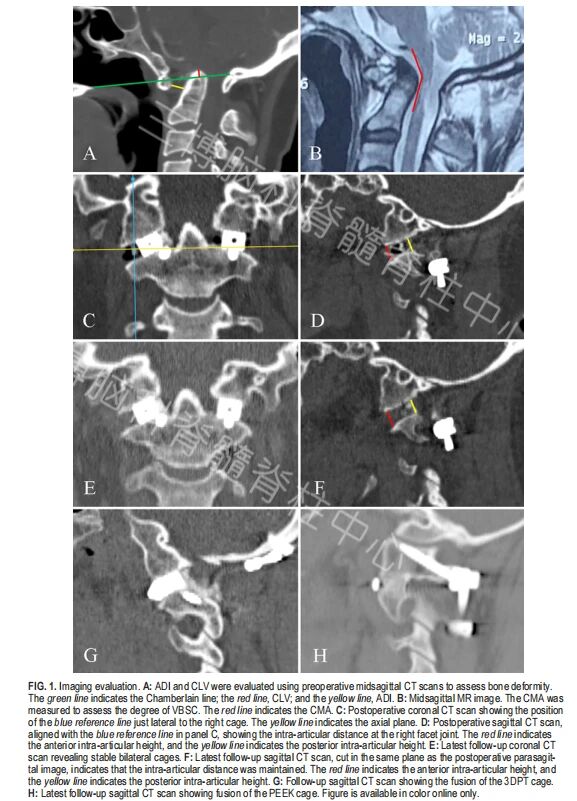

▲图1:影像学评估